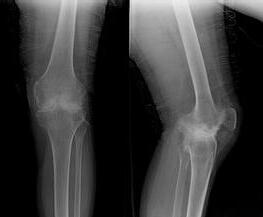

来院后,由王怀庆主任接诊,随后便为她做了详细的检查。X线示:双膝关节边缘及髌骨底呈唇样改变,相应关节面不光整;膝关节间隙呈内窄外宽。确诊:风湿性关节炎。王怀庆主任根据刘女士的病情和身体状况,为其...[详细]